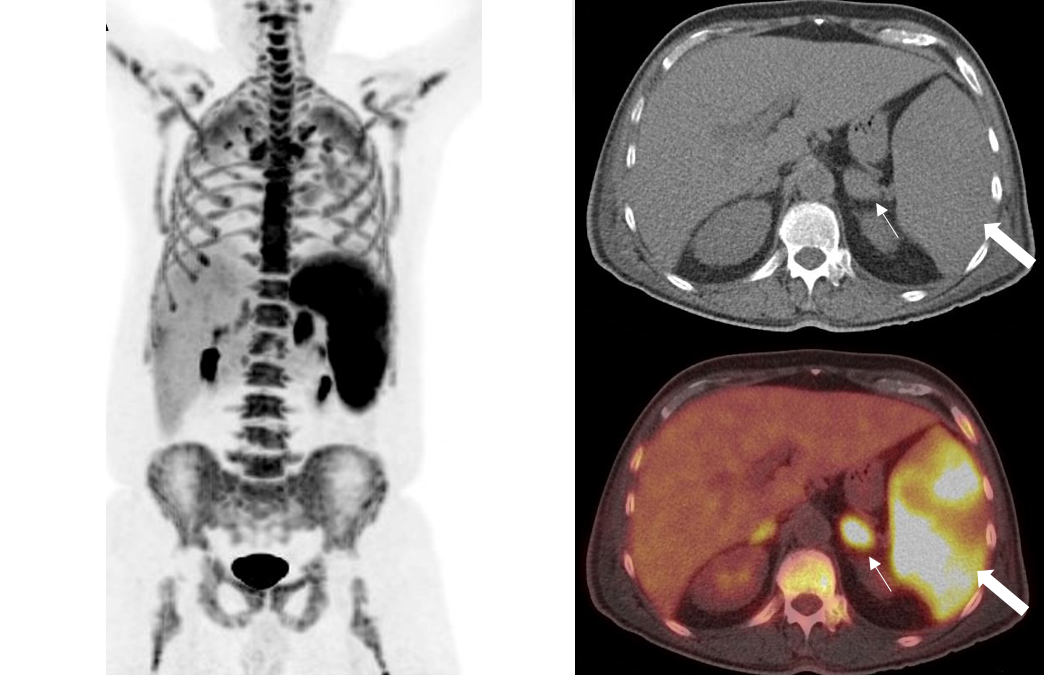

Extranodal lymphoma (Liver, spleen, adrenal glands and bone marrow): 18F-FDG PET/CT imaging A 68-year-old male was transferred to our hospital because of an impairment of his general condition, weight loss and fever in the last 20 days. Dyspnea and splenomegaly...